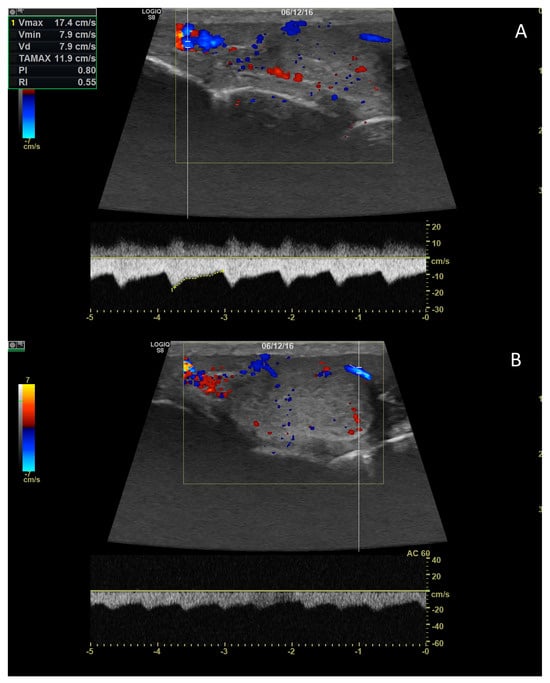

4.3. Relationship between Spectral Doppler Measurement and Dog’s Semen Quality

- Carrillo, J.; Soler, M.; Lucas, X.; Agut, A. Colour and Pulsed Doppler Ultrasonographic Study of the Canine Testis: Doppler Ultrasound Testis Dog. Reprod. Domest. Anim. 2012, 47, 655–659. [Google Scholar] [CrossRef]

- De Souza, M.B.; da Cunha Barbosa, C.; Pereira, B.S.; Monteiro, C.L.B.; Pinto, J.N.; Linhares, J.C.S.; da Silva, L.D.M. Doppler Velocimetric Parameters of the Testicular Artery in Healthy Dogs. Res. Vet. Sci. 2014, 96, 533–536. [Google Scholar] [CrossRef] [PubMed]

- Gloria, A.; Di Francesco, L.; Marruchella, G.; Robbe, D.; Contri, A. Pulse-Wave Doppler Pulsatility and Resistive Indexes of the Testicular Artery Increase in Canine Testis with Abnormal Spermatogenesis. Theriogenology 2020, 158, 454–460. [Google Scholar] [CrossRef] [PubMed]

- Gumbsch, P.; Holzmann, A.; Gabler, C. Colour-Coded Duplex Sonography of the Testes of Dogs. Vet. Rec. 2002, 151, 140–144. [Google Scholar] [CrossRef] [PubMed]

- Zelli, R.; Troisi, A.; Elad Ngonput, A.; Cardinali, L.; Polisca, A. Evaluation of Testicular Artery Blood Flow by Doppler Ultrasonography as a Predictor of Spermatogenesis in the Dog. Res. Vet. Sci. 2013, 95, 632–637. [Google Scholar] [CrossRef]